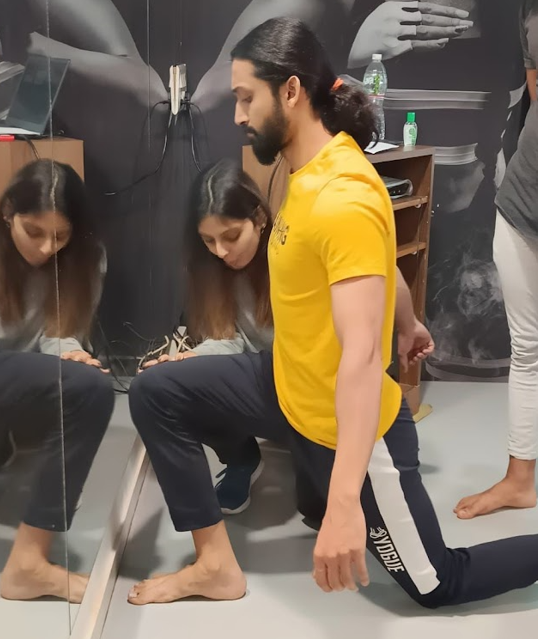

Highly Skilled Professional

Our team consists of experienced physiotherapists and podiatrists who stay updated with the latest techniques and advancements in their fields.

Individualized Treatment Plans

We believe in personalized care, tailoring our treatment plans to meet the unique needs and goals of each patient.

State-of-the-Art Facility

Our modern clinic is equipped with advanced technology and equipment to provide superior diagnostic and therapeutic services.

Patient Satisfaction

Our commitment to providing exceptional care has resulted in a high level of patient satisfaction and positive treatment outcomes.